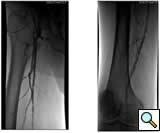

Case 4: A 67-year-old woman with diabetes and tissue loss in the foot secondary to pressure injury with poor healing. Angiogram through an antegrade approach shows a small vessel (average diameter 3 mm) with proximal occlusion and segmental stensoses (Figure 4A). After angioplasty followed by cryoablation, the proximal stenotic areas were treated with 5 mm diameter coronary self-expanding bare stents (Figure 4B). The foot has now healed.

![]() |

| Figure 4A | Figure 4B |